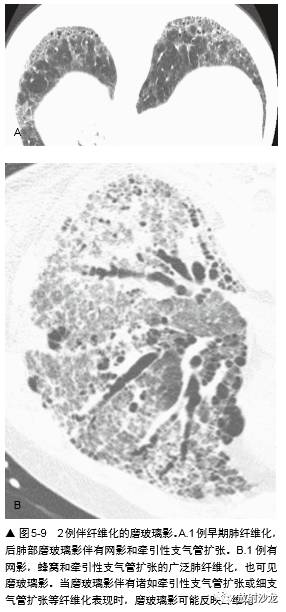

因为磨玻璃影反映存在纤维化或炎症,诊断 时要小心,仅在不伴有HRCT 纤维化表现,或以 磨玻璃影为主要表现时诊断(图 5-5 ~图 5-8)。如磨玻璃影仅见于有牵引性支气管扩张或蜂窝等 HRCT 的纤维化改变的肺区内,纤维化可能将使 主要的组织学异常(图5-4,图5-9)。例如,在 Remy-Jardin 等的一项研究中,所有 HRCT 上的磨 玻璃影区内有牵引性支气管扩张或细支气管扩张 的病例,活检都有纤维化。然而,在不伴有牵引 性支气管扩张的磨玻璃影区的病例中,肺活检时 92% 发现有活动性炎症。

亚急性或慢性症状病例中磨玻璃影最常见的病因包括(表 5-1):间质性肺炎,如非特异性间 质性肺炎(NSIP)(图 5-8,图5-11),特发性 或其他特异性疾病,如硬皮病或其他胶原血管病,脱屑性间质性肺炎(DIP)(图 5-12) ,呼吸细支气管炎-间质性肺疾病(RB-ILD),过敏性肺炎(HP)(图 5-5,5-13), 机化性肺炎(OP),药物反应,慢 性嗜酸性肺炎(图 5-14),淋巴样间质性 肺炎(LIP),Churg-Strauss综合征, 类脂质肺炎(图5-15)和慢性或反复性吸入性肺炎,非黏液性和黏液性肺腺癌(图5-16) , 结节病,和肺泡蛋白沉着症(PAP)(图 5-17)。

在有磨玻璃影的病例中,组织学异常的类型 根据疾病的典型组织学表现而异,无特异性组织学改变(表 5-2)。在 NSIP、硬皮病或 其他胶原血管病病例中,许多研究曾结合CT 上 的磨玻璃影和活检结果、治疗反应和病例的生存期。在间质性肺炎病例的组织学研 究中曾显示,大部分磨玻璃影和肺泡壁或肺泡内炎症相关。例如,在一项Wells 等的硬皮病研究中,HRCT 上的致密度增加和7 例活检中4例的明显炎症相关,而在HRCT 上的网影中,13 例中12 例为纤维化。另一项14 例HRCT 表现为 磨玻璃影的特发性肺纤维化(IPF)病例中,活检 12 例有炎症。在寻常性间质性肺炎(UIP)病 例中,磨玻璃影伴有不等的肺纤维化;有磨玻璃 影的DIP 病例在很大程度上反映肺泡内有巨噬细胞。